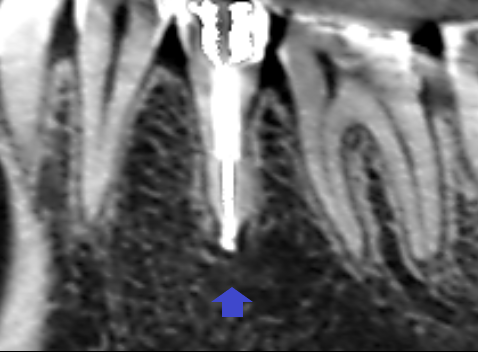

精密根管治療6カ月後の経過観察時の矢状断のCT画像です。下顎第二小臼歯の矢印の先にあった膿の影が消え、歯槽骨が再生しています。